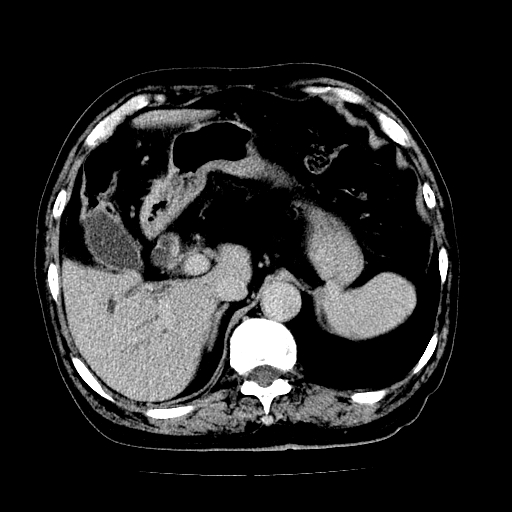

男,71岁,皮肤黄染四天。

肝内外胆管及胆总管上段扩张,考虑为梗阻所致,建议mrcp检查。

考虑胆总管癌并肝内外胆管扩张。

胰腺上端胆总管内见软组织影,强化不明显,结合临床,还是考虑低位梗阻性黄疸,胆总管癌可能性大